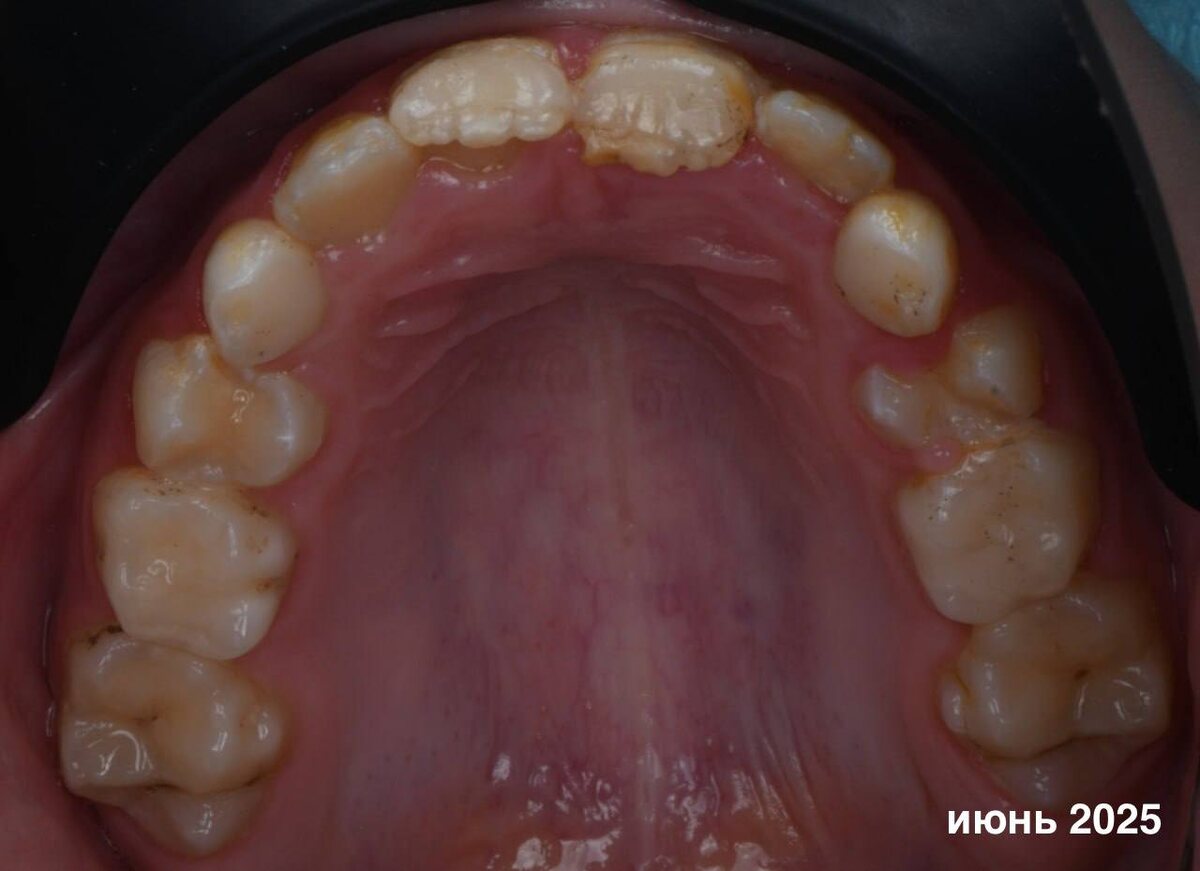

Но мы можем все исправить! История нашей юной пациентки классический пример, почему так важно наблюдение после травмы молочных зубов. Годы назад удар привел к дилацерации — искривлению коронковой части зубов формирующихся постоянных резцов. Когда зубы прорезались, стало понятно: без лечения не обойтись. Первично девочку осмотрел ортодонт (спасибо коллеге за внимательность и направление), после чего пациентка пришла ко мне. Основная задача была максимально щадящей — сохранить жизнеспособность зубов и дать корням возможность продолжить формирование. Что я сделала 👉 • Провела пульпотомию (ампутацию коронковой части пульпы) зубов 11 и 21, • Выполнила восстановление композитным материалом. Лечение было непростым: ребёнок быстро уставал. Но ее храбрость и терпение родителей дало результат. Мы сразу обсудили, что после полного прорезывания, следующий этап – коррекция реставраций, а также рекомендовали продолжить работу с другими зубами.

История нашей юной пациентки классический пример, почему так важно наблюдение после травмы молочных зубов. Годы назад удар привел к дилацерации — искривлению коронковой части зубов формирующихся постоянных резцов. Когда зубы прорезались, стало понятно: без лечения не обойтись.

Первично девочку осмотрел ортодонт (спасибо коллеге за внимательность и направление), после чего пациентка пришла ко мне. Основная задача была максимально щадящей — сохранить жизнеспособность зубов и дать корням возможность продолжить формирование.

• Провела пульпотомию (ампутацию коронковой части пульпы) зубов 11 и 21,

• Выполнила восстановление композитным материалом.

Мы сразу обсудили, что после полного прорезывания, следующий этап – коррекция реставраций, а также рекомендовали продолжить работу с другими зубами.